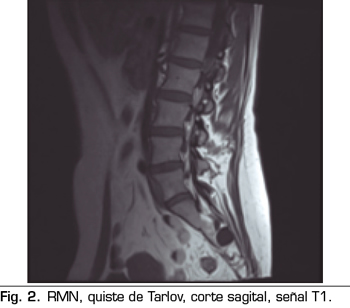

Se realiza una RMN donde no se observan alteraciones estructurales que justifiquen las dolencias que presenta. Como hallazgo casual se describen quistes de Tarlov a nivel de S2. Se solicita una valoración por el servicio de neurocirugía, quienes dudan que la clínica sea consecuencia de los quistes (Figuras 1 y 2).

Una de las causas de dolor crónico a tener en cuenta son los “quistes perineurales” o “quistes de Tarlov”. Desde su primera descripción en 1938, son numerosos los artículos en los que se hace referencia. Se trata de lesiones nerviosas que se producen más frecuentemente en la zona sacra (8). En un estudio de Paulsen RD sobre la prevalencia y el drenaje de los quistes de Tarlov, se observó que en 500 pacientes que se sometían a una Resonancia Magnética (RMN) por dolor lumbar, el 5 % presentaba quistes de Tarlov y un 20 % de esos pacientes padecían síntomas relacionados con ellos (9,10). El diagnóstico suele ser casual mediante RMN; la cifra es variable debido a que solo se solicita a aquellos pacientes que presentan dolor lumbar crónico. Dicha técnica es más sensible que la tomografía axial computerizada (11,12).

No obstante, debemos tener en cuenta las variaciones anatómicas como son los quistes de Tarlov, a expensas de las capas más internas de las meninges, la piamadre y el aracnoides. Estos quistes principalmente se sitúan en la zona sacra y lumbar, y suelen diagnosticarse de manera incidental en el transcurso de una RMN. Aunque la clínica producida por los mismos no es frecuente, se deben tener en cuenta como posible diagnóstico diferencial ante posible dolor lumbar crónico.